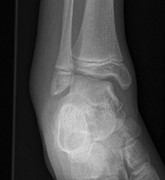

Unusual fracture combination in a paediatric acute ankle (combined medial talar compression fracture with medial malleolus fracture in an immature skeleton): a case report

Sebastien Crosswell and others

Journal of Surgical Case Reports, Volume 2014, Issue 10, October 2014, rju100, https://doi.org/10.1093/jscr/rju100